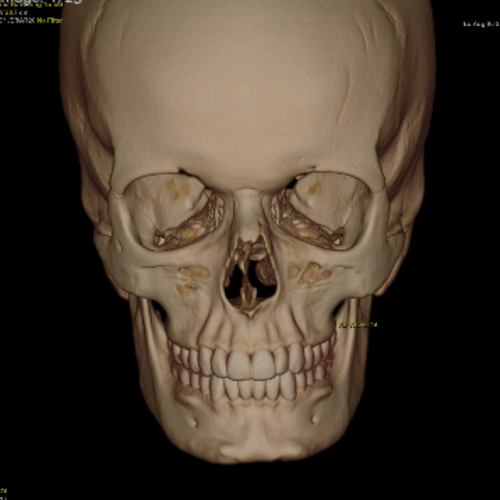

I'm scheduled to get mandible contouring, sliding genioplasty, rhinoplasty, and cheek implants in about a month but I'm wondering if this is a bad plan. any hardmaxxing advice? Attached images are from my ct scan for surgery.